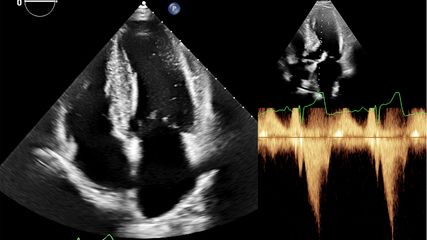

Die beiden Hauptpfeiler der PVE-Diagnostik sind Blutkulturen zur Detektion einer systemischen Infektion und der spezifische echokardiografische Nachweis von intrakardialen Vegetationen, neu aufgetretenen Klappeninsuffizienzen und vorhandenen Abszessen. Eine Verbesserung der Bildgebung hat zur besseren Detektion der endokardialen Beteiligungen der IE geführt. Eine echokardiografische Untersuchung sollte bei allen Patienten mit klinischem Verdacht auf Endokarditis durchgeführt werden, wobei die transösophageale Echokardiografie (TEE) der transthorakalen Echokardiografie (TTE) meist überlegen ist und den goldenen Standard darstellen sollte. Ergänzend zur Echokardiografie finden sich in den neuen Leitlinien auch CT und PET-CT als Bildgebung und wurden in die modifizierten Duke-Hauptkriterien aufgenommen (Abb. 1). F-FDG-PET oder SPECT-CT mit radioaktiv markierten Leukozyten erhöhen die Sensitivität für die Diagnostik einer PVE.9 Aufgrund von unspezifischen Entzündungsreaktionen postoperativ kann dieses Verfahren allerdings erst drei Monate nach erfolgtem Eingriff sinnvoll und zielführend angewendet werden.